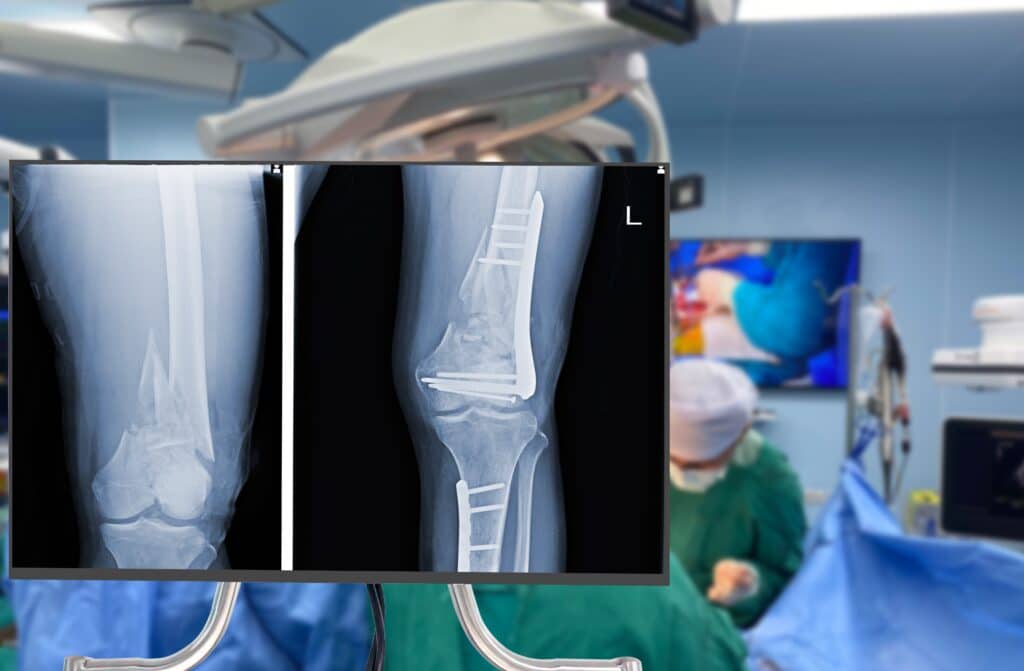

Whether a fracture (broken bone) is caused by a fall, a car accident, or some other type of trauma, an orthopaedic surgeon has the expertise to help repair the broken bone and get you back on your feet. The most common type of fracture treatment is to set the bone into place and then immobilise it with a cast or splint. Depending on the severity of the fracture, the orthopaedic surgeon may need to perform surgery to properly set the bone in place, known as open reduction internal fixation (ORIF). During this procedure, the surgeon will make an incision to expose the fracture and manually set the bone pieces into place. Metal plates, screws, or pins are then used to keep them in position while they heal. Surgery may also be necessary to repair any soft tissue damage that has occurred because of the fracture.

X-ray of leg with surgery in background.